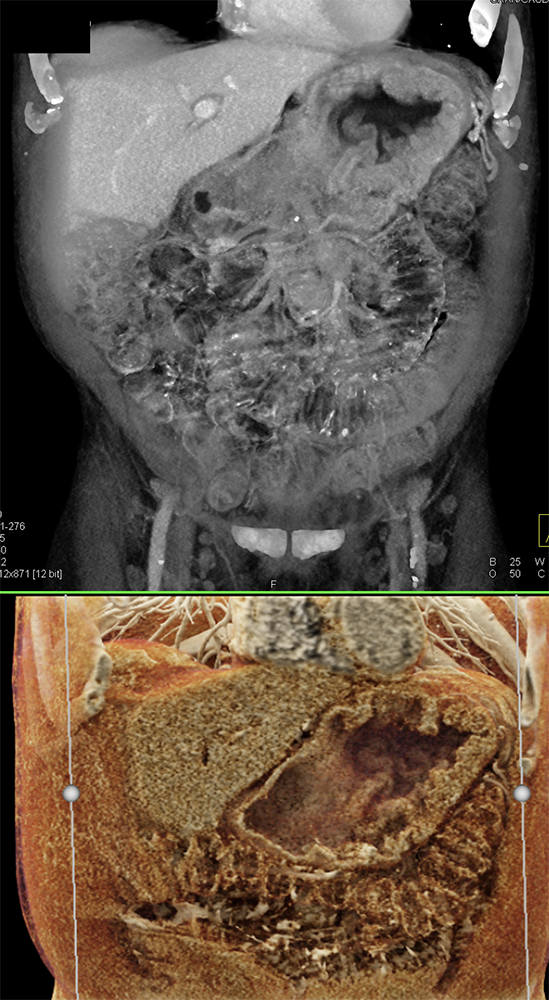

Watermelon stomach (WMS), or gastric antral vascular ectasia (GAVE) ![]() |

“Gastric antral vascular ectasia primanily affects women (9:1 female-to-male ratio) aged 56-76 years, and is associated with liver cirrhosis (37%) and achlorhydnia (35%). The usual symptoms are iron-deficiency anemia and melena due to chronic gastrointestinal bleeding from the dilated, superficial, and easily traumatized vessels. Antrectomy is curative, but endoscopic treatment with heat probes or lasers has shown promise.” Gastric antral vascular ectasia ("watermelon stomach"): radiologic findings. Urban BA, Jones B, Fishman EK, Kern SE, Ravich WJ. Radiology. 1991 Feb;178(2):517-8. |

“In our patient, the findings of prominent mucosal folds extending from the pylonic channel on upper gastrointestinal series and the thickened antral wall on CT scans correlate well with the known pathologic appearance of gastnic antral vascular ectasia. Histologically, antral thickening results from a combination of foveolar and fibromuscular hyperplasia. Grossly, the antral fold prominence appears to result from bunching of the mucosa in the thickened, hypercontractile antrum.” Gastric antral vascular ectasia ("watermelon stomach"): radiologic findings. Urban BA, Jones B, Fishman EK, Kern SE, Ravich WJ. Radiology. 1991 Feb;178(2):517-8. |

“Watermelon stomach (WMS), or gastric antral vascular ectasia, is an uncommon but clinically important cause of chronic occult or overt gastrointestinal (GI) blood loss. Patients typically present with symptomatic anemia and hemoccult positive stools. Although the diagnosis is based primarily on the typical endoscopic appearance, the lesion may be overlooked on initial evaluation or interpreted as "gastritis." Gastric biopsy may be helpful in confirming the diagnosis by showing vascular ectasia, typically without inflammation. WMS is idiopathic but is often associated with autoimmune diseases or cirrhosis of the liver. The majority of patients with classic WMS are elderly and female.” |

“Gastric antral vascular ectasia (GAVE) is a rare entity with unique endoscopic appearance described as "watermelon stomach." It has been associated with systemic sclerosis but the pathophysiological changes leading to GAVE have not been explained and still remain uncertain.” Gastric Antral Vascular Ectasia in Systemic Sclerosis: Current Concepts. Parrado RH et al. Int J Rheumatol. 2015;2015:762546. |